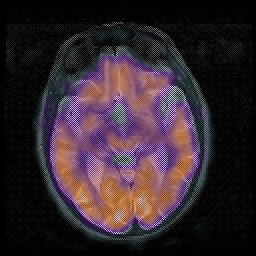

Huntington's Chorea, MR -- Slice #8

[Home][Help][Clinical] Slice 8